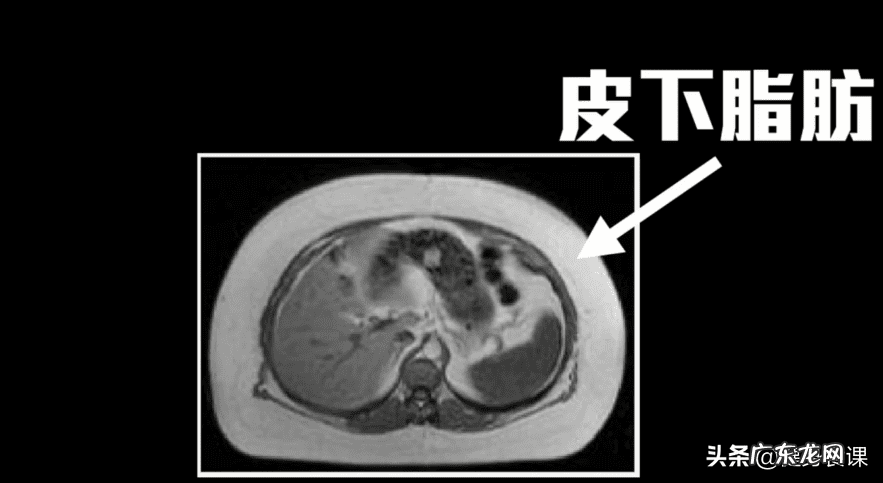

与糖尿病 , 慢性发炎 , 心血管疾病的有很紧密的关联 , 但堆积在皮下的脂肪 , 对于我们健康来说 , 不但害处比内脏脂肪小很多 , 反而在一定程度上能够保护我们的代谢健康 。

抽脂手术所能移除的呢 , 都是皮下脂肪 , 而内脏脂肪的一点都不会变少 。也难怪 , 就算这些人抽了十公斤的脂肪 , 他们的健康 , 一点也没有改善 。